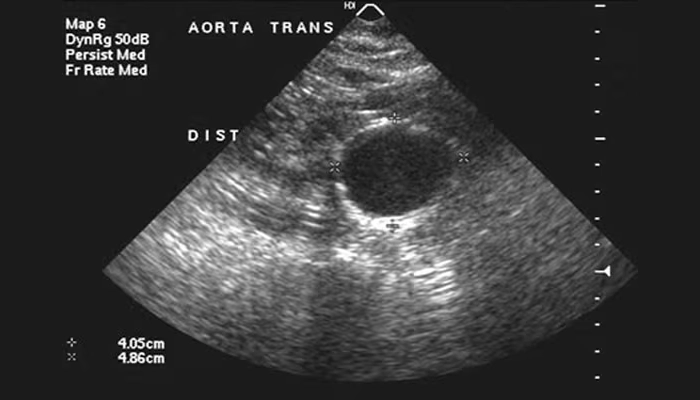

4.1. Siêu âm bụng

-

Là phương pháp phổ biến và an toàn nhất để phát hiện phình động mạch chủ bụng.

Độ chính xác cao, không xâm lấn, chi phí thấp.

Thường dùng để tầm soát cho nam giới trên 65 tuổi có tiền sử hút thuốc.

Hình ảnh siêu âm của một bệnh nhân bị phình động mạch chủ bụng